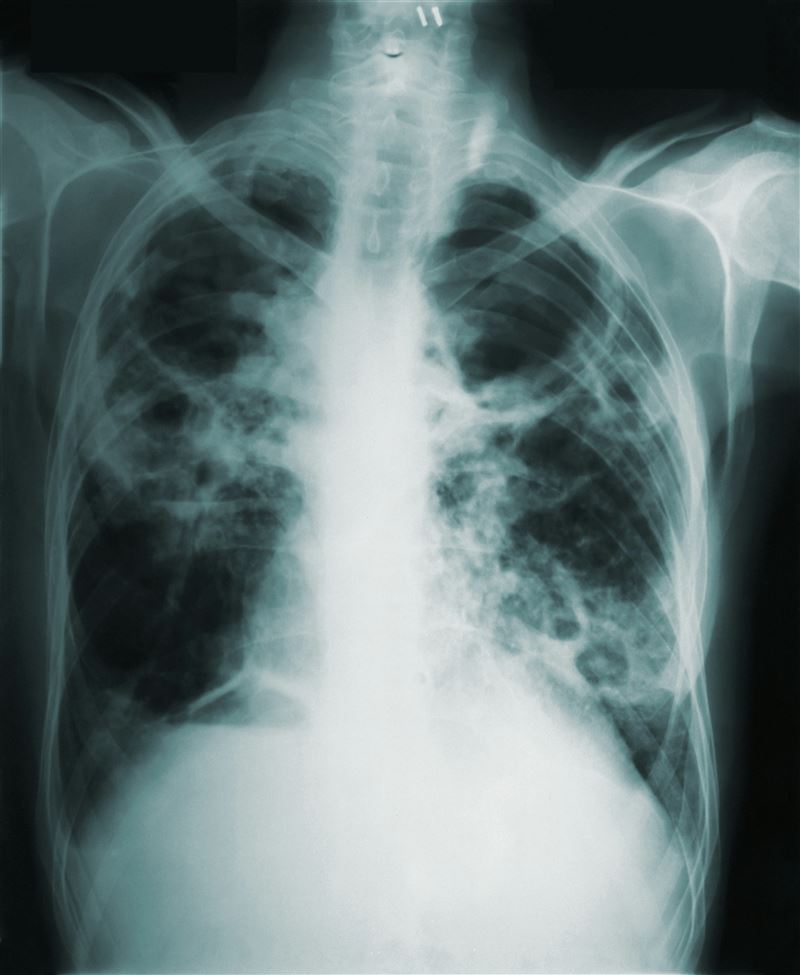

台大校園傳出肺結核確診個案。(圖/資料照)

台大校園近日傳出肺結核確診個案,北市衛生局今(4)日表示,目前正積極進行匡列接觸者;疾管署則澄清此為單一確診個案,並非校園群聚事件。肺結核(俗稱肺癆)作為流傳超過600年的慢性傳染病,可怕之處在於發病初期症狀極不明顯,容易被誤認為感冒或一般疲勞而忽略,若不治療,3年內死亡率高達5成。以下整理肺結核的10大QA,一次看懂怎麼預防、怎麼處理。

肺結核(Tuberculosis, TB)是一種由結核分枝桿菌(Mycobacterium tuberculosis)引起的慢性傳染病,能長期潛伏在體內。最常侵犯肺部,也可能擴散至淋巴結、骨骼、腎臟等全身任何器官(稱作肺外結核)。